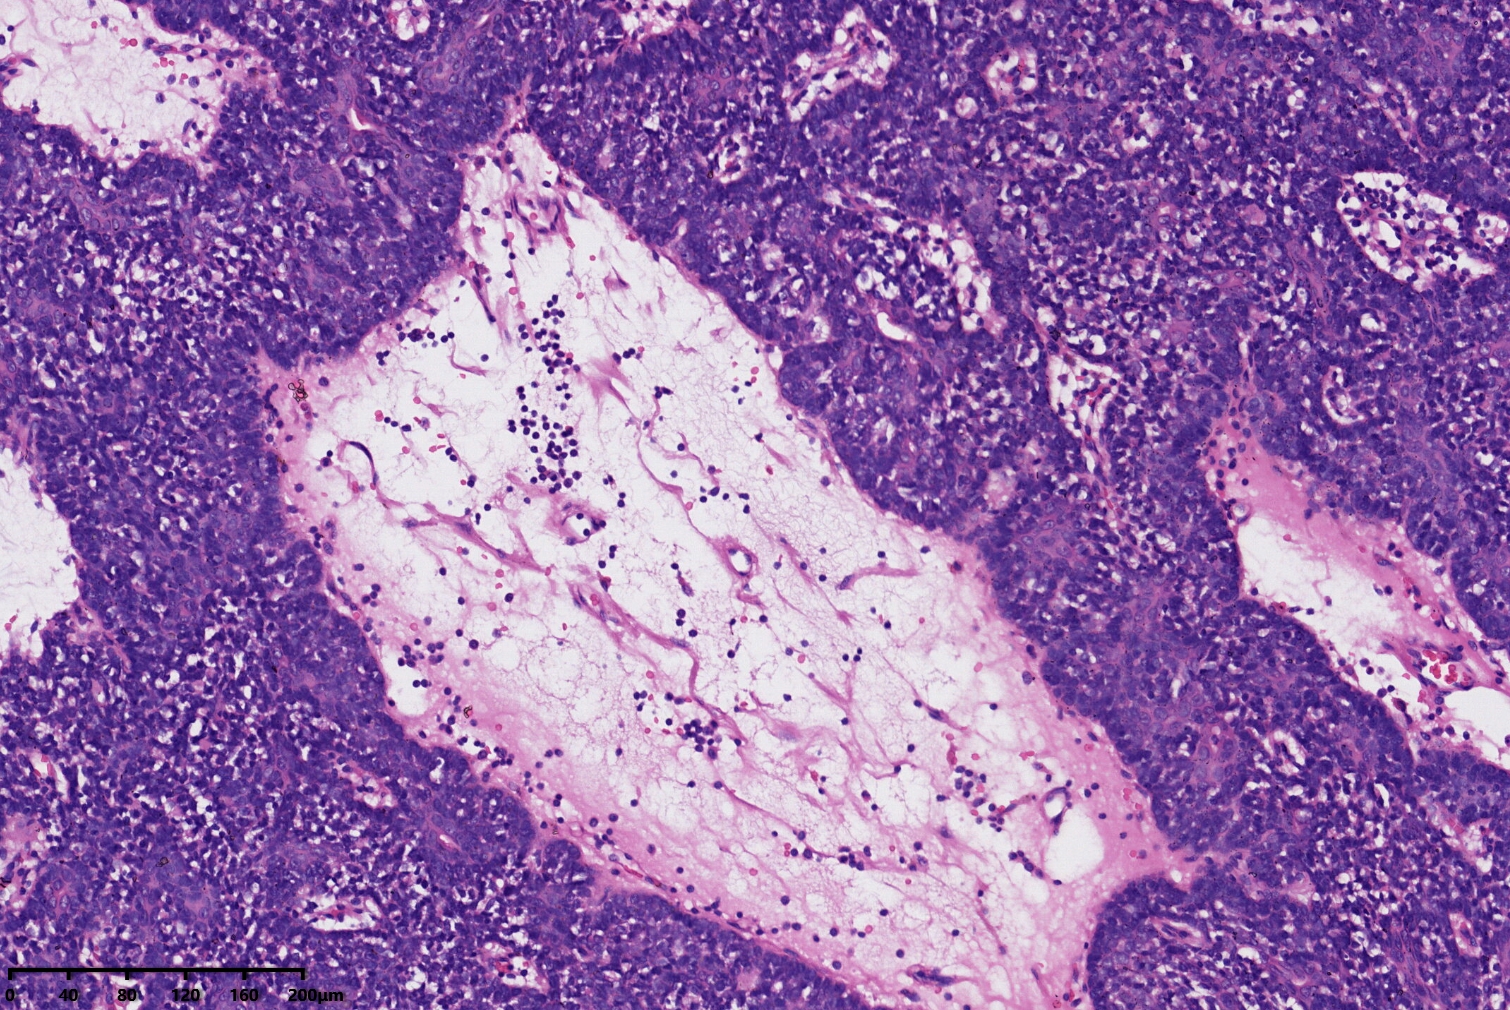

汗腺腺瘤?

背部包块

同意,有的区域像透明细胞汗腺瘤

小汗腺螺旋腺瘤